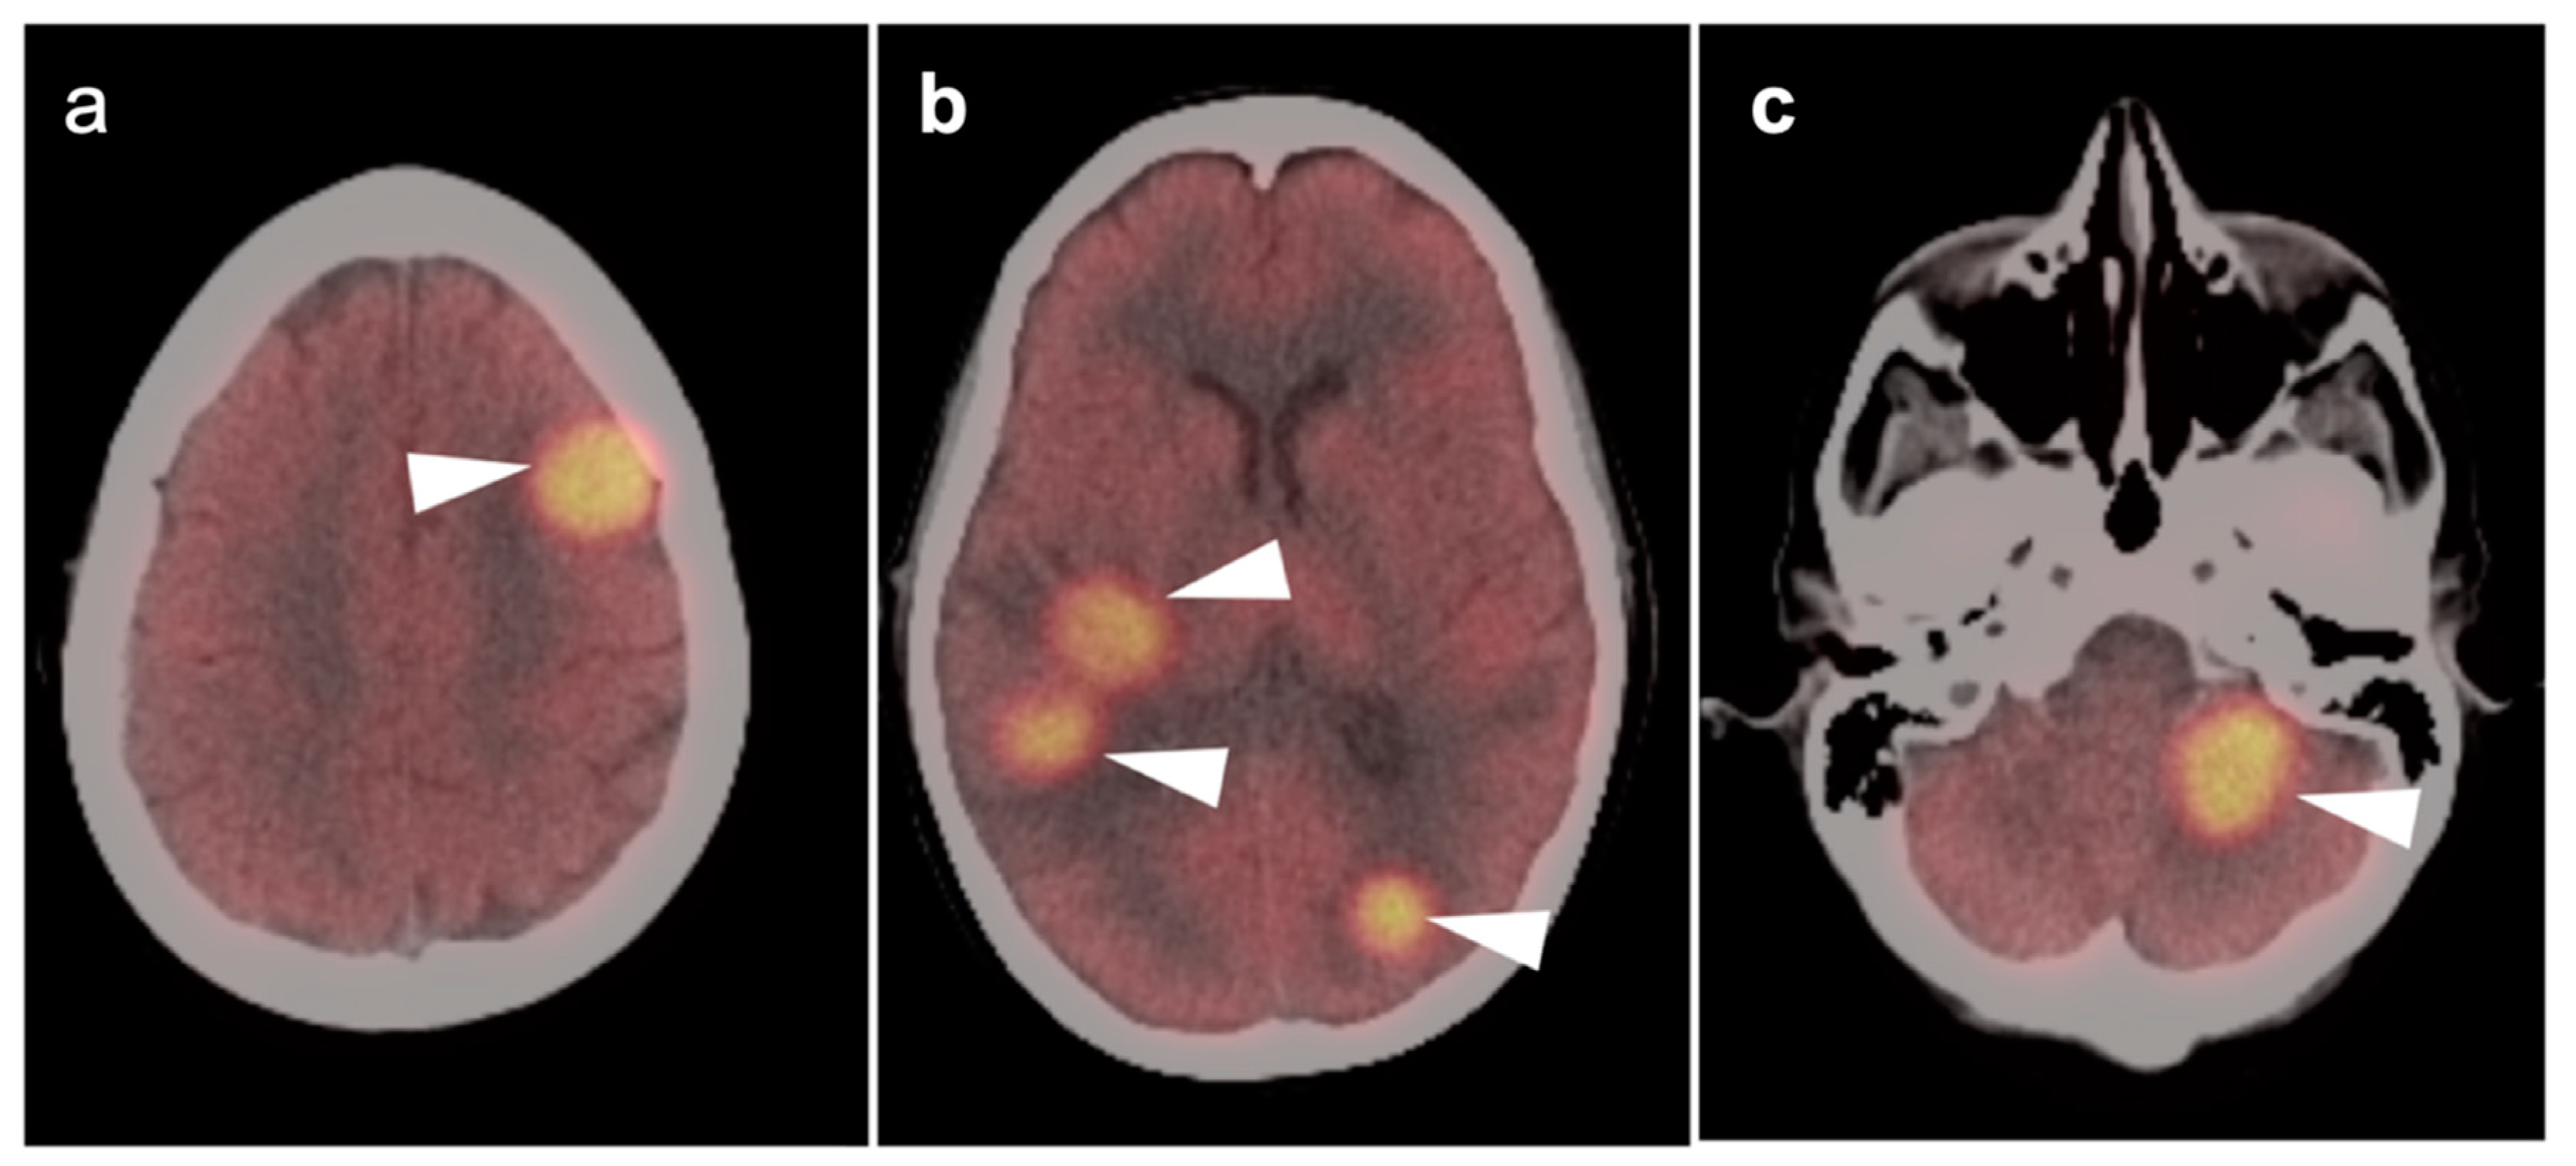

3.5. Brain Metastases

3.6. Response to Therapy

- Galldiks, N.; Langen, K.-J.; Albert, N.L.; Chamberlain, M.; Soffietti, R.; Kim, M.M.; Law, I.; Le Rhun, E.; Chang, S.; Schwarting, J.; et al. PET imaging in patients with brain metastasis-report of the RANO/PET group. Neuro-Oncology 2019, 21, 585–595. [Google Scholar] [CrossRef]